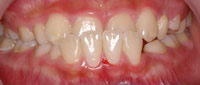

3.永久歯がまっすぐに出てこない場合

叢生